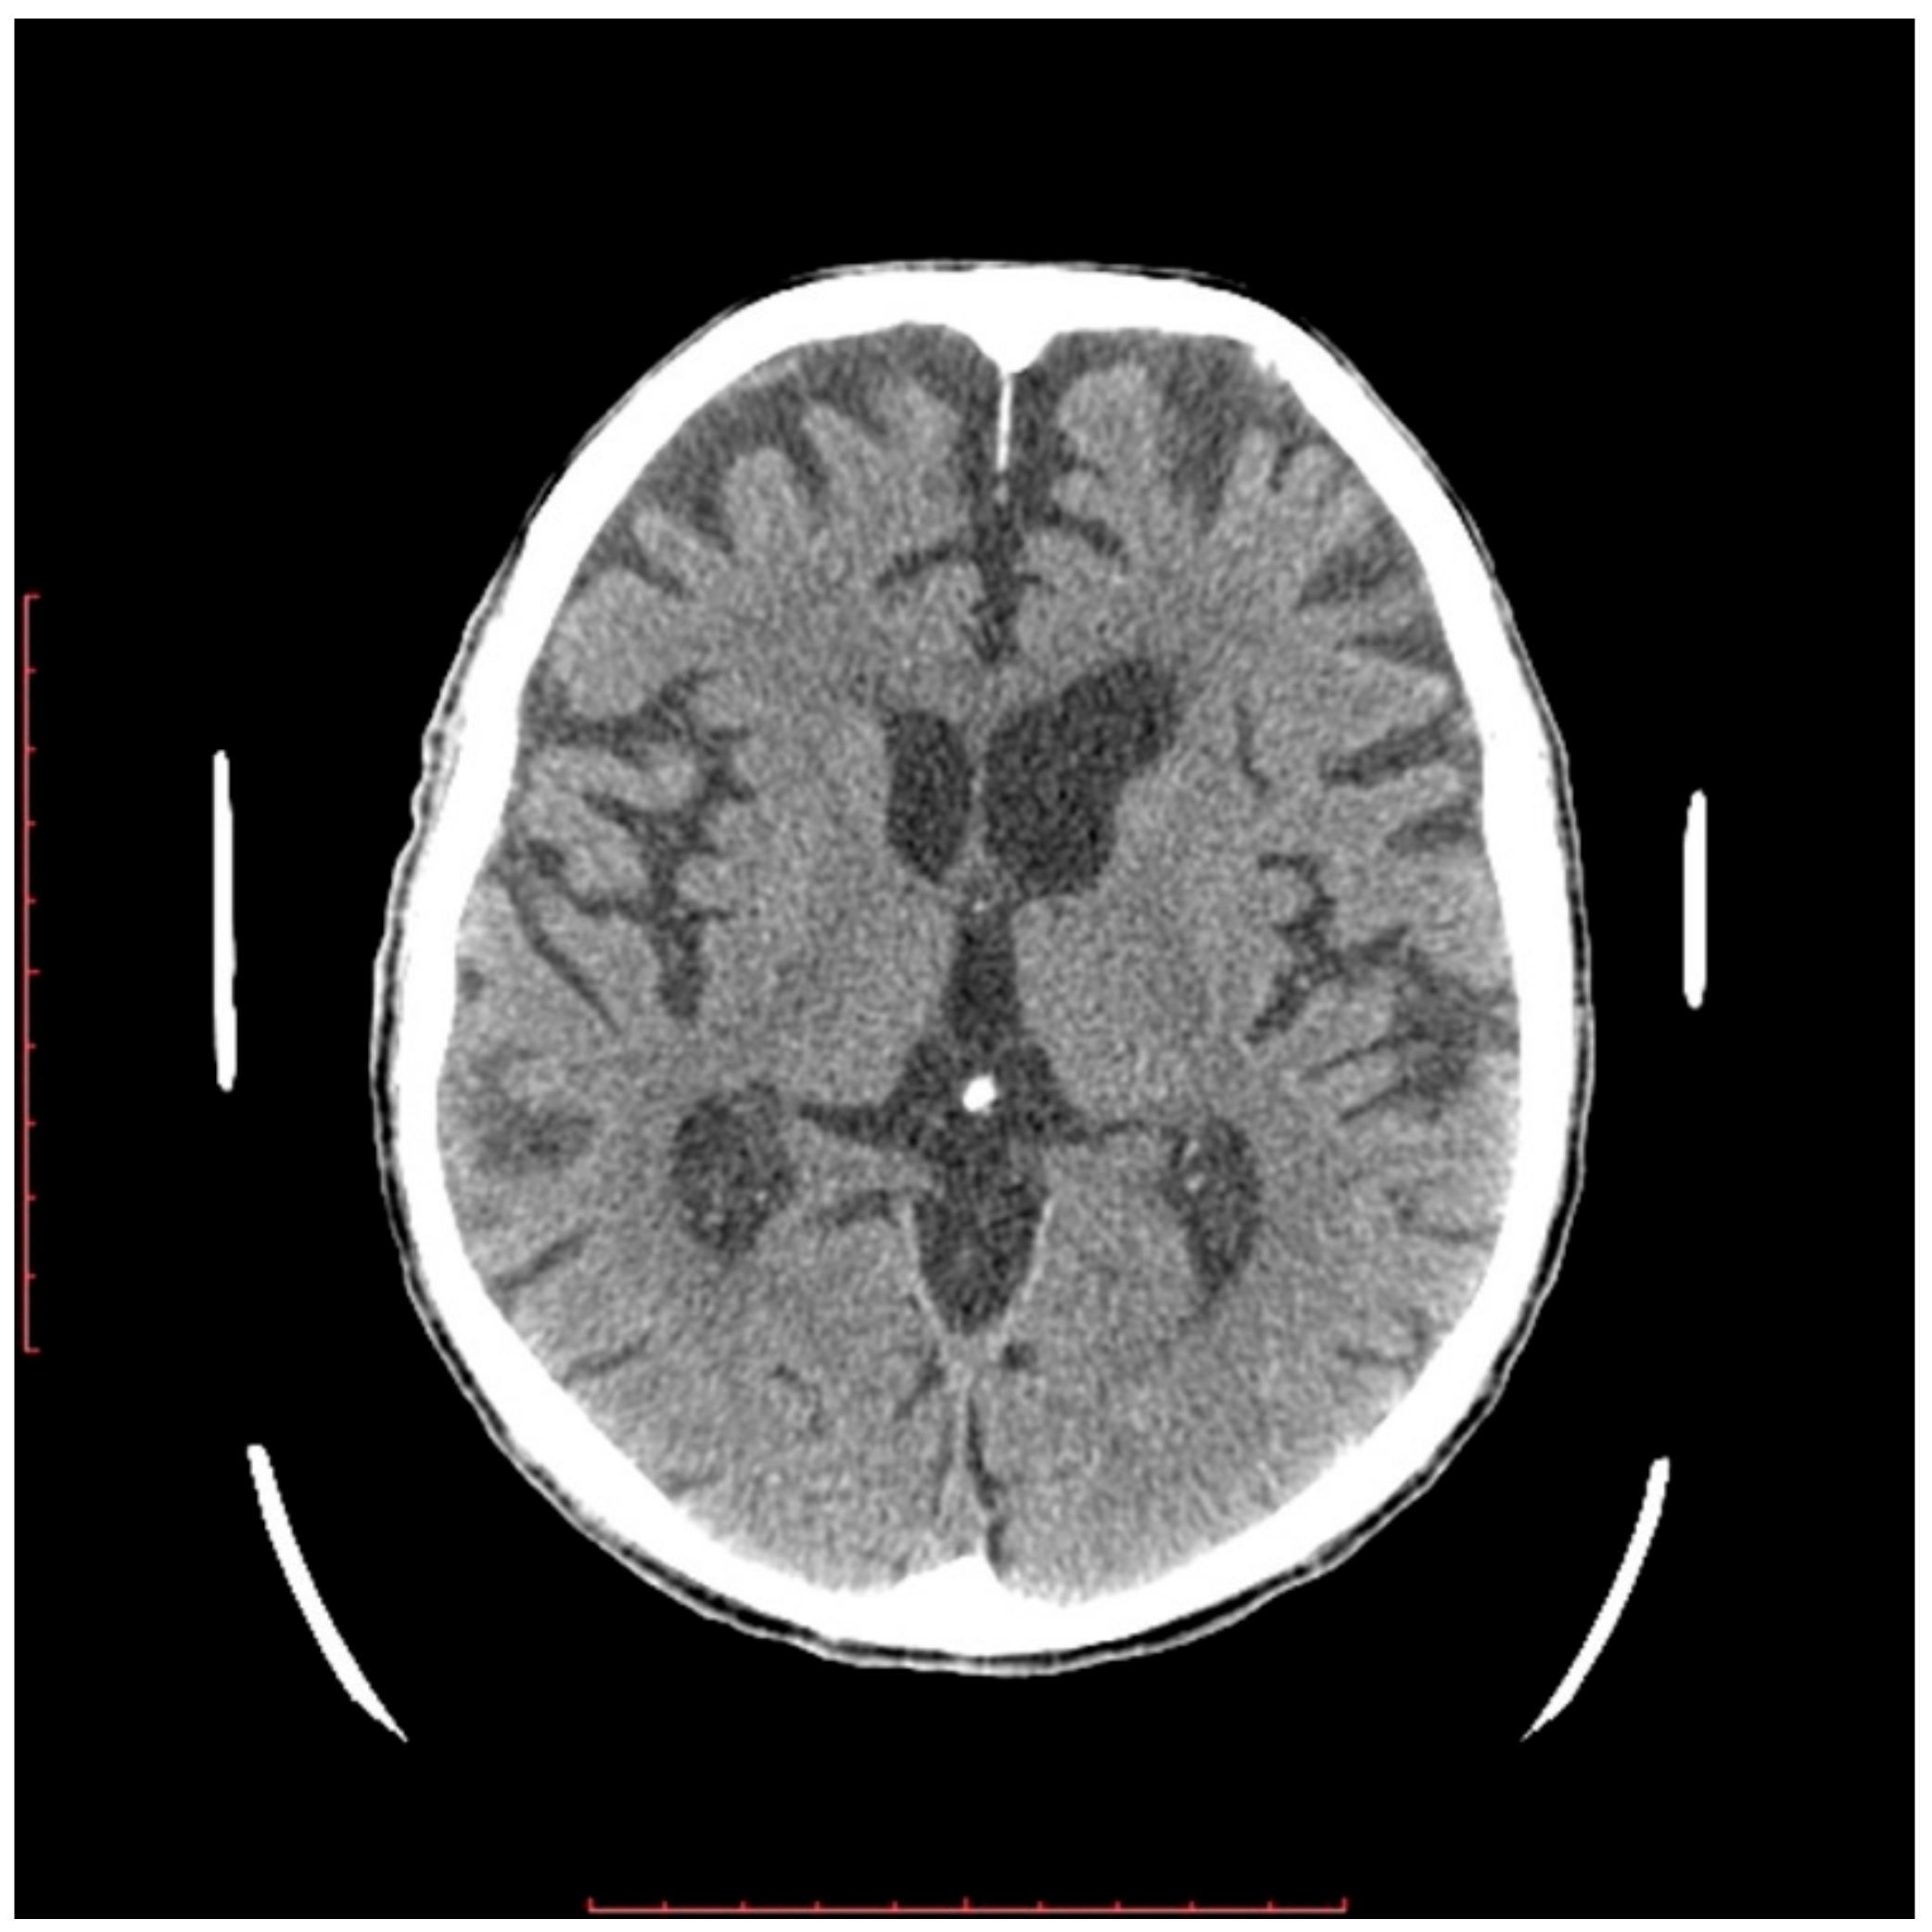

2.2. Neurological Examination

4.2. The Neurological Conditions